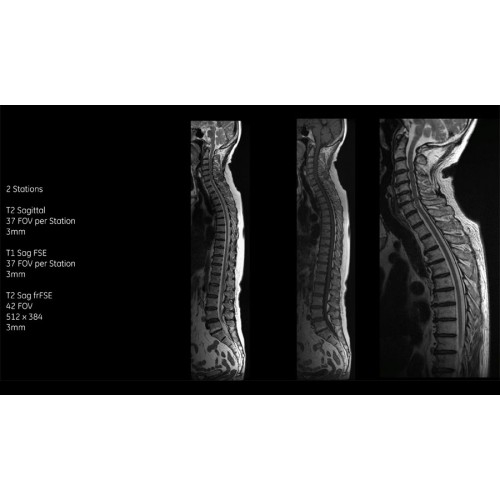

- Технология Digital Surround Technology (DST) — это новая технология объемной оцифровки данных, объединяющая сигналы от каждого элемента катушки. Прекрасное соотношение сигнал/шум и чувствительность поверхностных катушек в сочетании с превосходной однородностью и высокой проникающей способностью встроенной радиочастотной катушки — все это позволяет создавать качественные изображения не только позвоночника, но и всего тела.